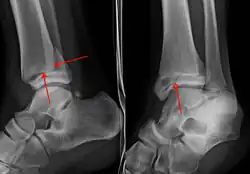

On clinical examination, it is important to evaluate the exact location of the pain, the range of motion and the condition of the nerves[11]. It is important to palpate the calf bone (fibula) because there may be an associated fracture proximally (Maisonneuve fracture)[12], and to palpate the sole of the foot to look for a Jones fracture at the base of fifth metatarsal [13]Evaluation of ankle injuries for fracture is done with the Ottawa ankle rules, a set of rules that were developed to minimize unnecessary X-rays.[14] There are three x-ray views in a complete ankle series: anteroposterior, lateral, and oblique [15]. The mortise view an anteroposterior x-ray taken with the ankle internally rotated until the lateral malleolus is on the same horizontal plane as the medial malleolus, resulting in a position where there normally is no superimposition of tibia and fibula on each other.[16]

On X-rays, there can be a fracture of the medial malleolus, the lateral malleolus, or of the anterior/posterior margin of the distal tibia. [17] If both the lateral and medial malleoli are broken, this is called a bimalleolar fracture[18]. If the posterior malleolus is also fractured, this is called a trimalleolar fracture. [19]